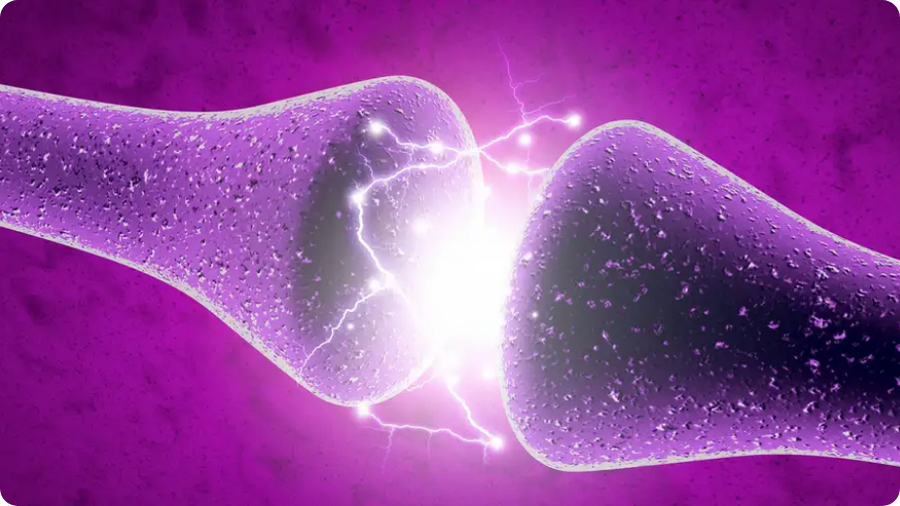

Sí, ¡y es un avance impresionante! 🧠🔬 Investigadores de la Universidad de Massachusetts Amherst han desarrollado neuronas artificiales que imitan de forma casi exacta el comportamiento eléctrico de las neuronas humanas. Aquí te cuento lo más destacado:

- Están hechas con nanocables de proteínas cultivadas a partir de bacterias generadoras de electricidad.

- Operan con voltajes similares a los de las neuronas reales, lo que permite una comunicación directa con sistemas biológicos.

- Su diseño bioinspirado permite que sean energéticamente eficientes, lo que las hace ideales para aplicaciones médicas y computacionales.